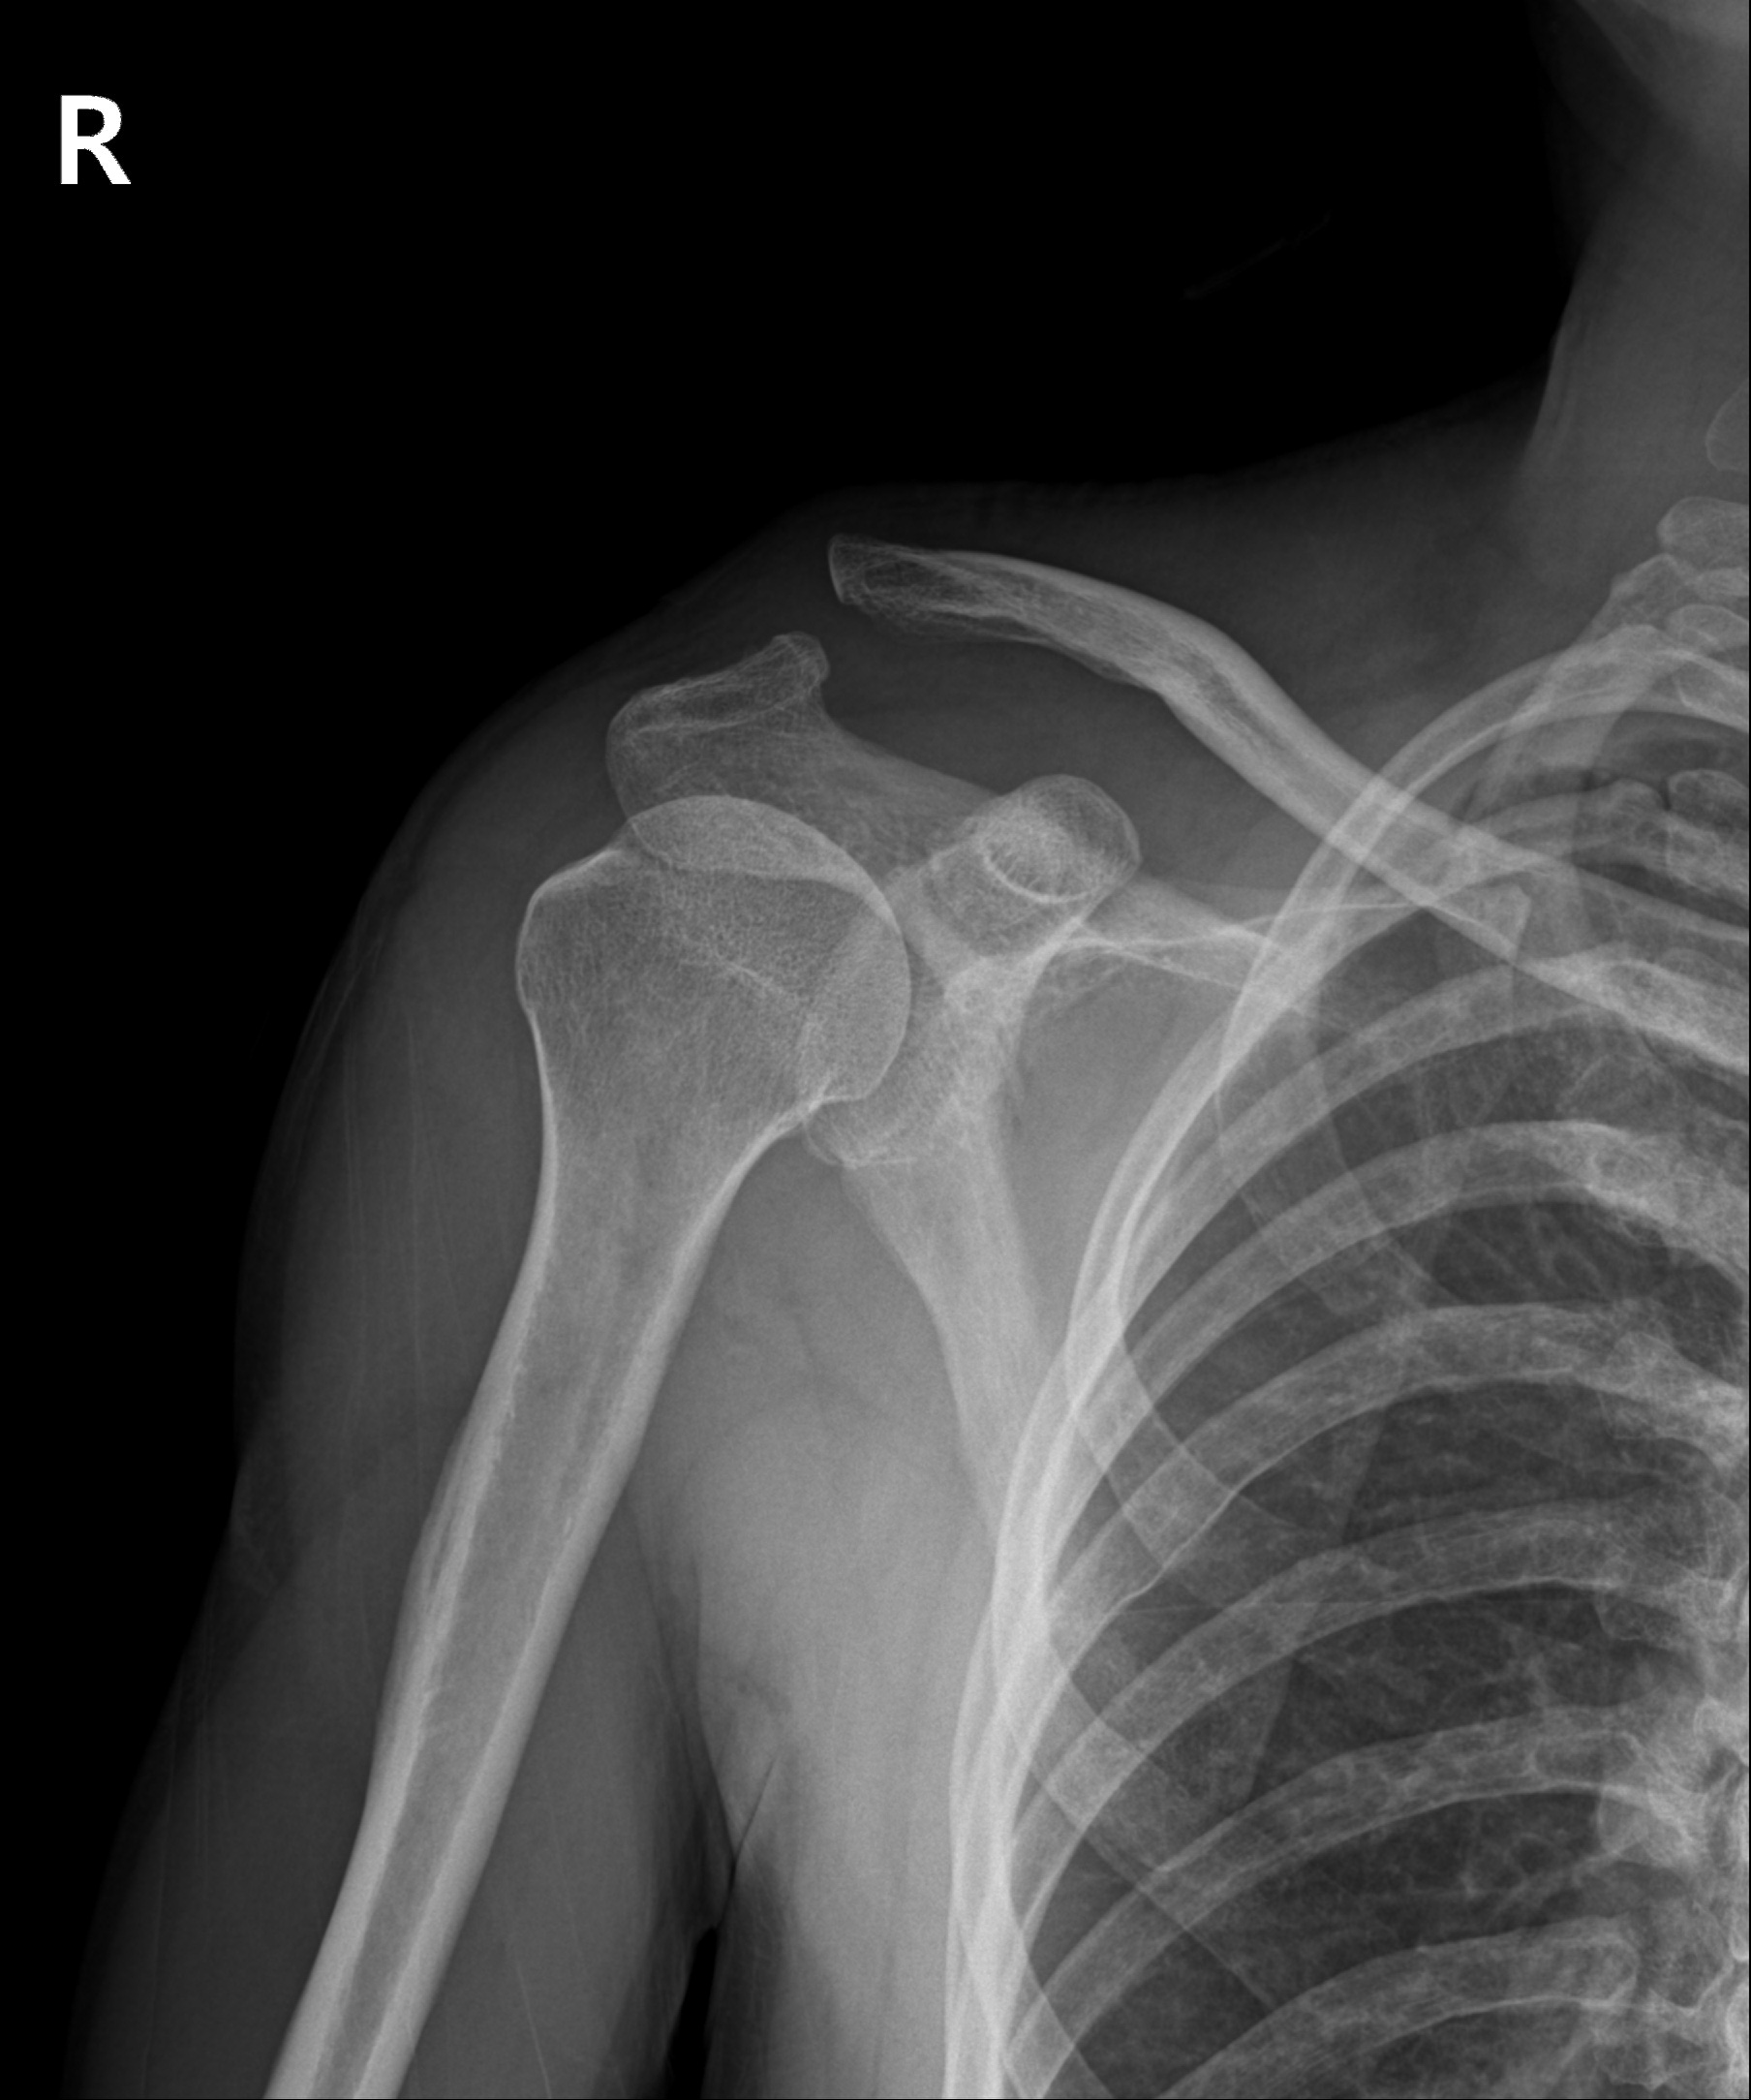

견쇄관절 탈구

2022.10.04

2022.12.27